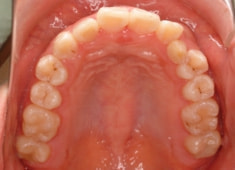

治療後(1年12ヶ月後)